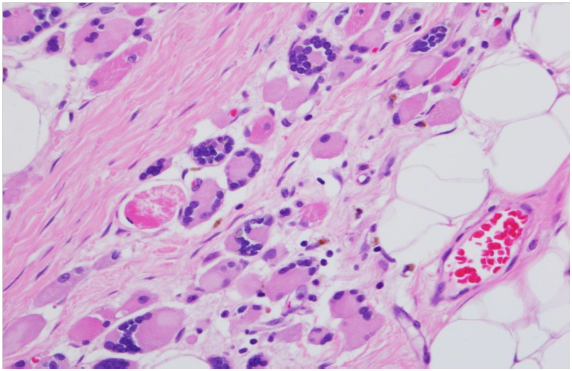

We report a case of a 63 year old female, with history of Stage I right breast invasive lobular carcinoma diagnosed twelve years previously, status post bilateral mastectomies with tram flap placement from the thigh. She has no history of familial breast cancer. She presents with a right chest wall nodule. The chest wall incisional biopsies and right breast tram pedicle needle core biopsies reveal invasive well differentiated ductal carcinoma grade 1 (Nottingham score, 1 + 2 + 1 = 4). The patient undergoes right tram flap mastectomy measuring 16 x 15.5 x 3.1 cm in greatest dimensions and weighing 337 grams. The posterior surface of the specimen displays strips of skeletal muscle fibers. The cut surface shows linear gray white fibrous area measuring 4.7 cm in length and 2.5 cm in diameter corresponding to the tracking scar of the needle core biopsy, involving the upper inner quadrant and abutting the posterior surface. Well differentiated glands extend into the pectoralis major muscle fibers (Figures 1 & 2). The invasive ductal carcinoma grade 1 (Nottingham score, 1 + 2 + 1 = 4) is seen in all sections from the tracking scar, which measures 4.7 cm in greatest dimension (Figure 4). The invasive ductal carcinoma demonstrates perineural involvement (Figure 3), vessel wall invasion and microcalcifications. The focal residual breast tissue shows fibrocystic change, atrophy and biopsy site changes (Figures 5 & 6).

Our patient, a 63 year old female, had a history of right sided stage 1 invasive lobular carcinoma. She had bilateral mastectomies with prophylactic simple mastectomy of the left breast and tram flap replacement. Twelve years later, she presents with a right sided chest nodule. The chest wall incisional biopsies and right breast tram pedicle needle core biopsies reveal invasive well differentiated ductal carcinoma grade 1 (Nottingham score, 1 + 2 + 1 = 4) (Figure 4). The subsequent right tram flap mastectomy shows well differentiated glands involving the pectoralis major muscle (Figures 1 & 2), perineural extension (Figure 3), vessel wall invasion, and microcalcifications. The tumor measures 4.7cm in the greatest dimension. The residual breast tissue shows fibrocystic changes, biopsy site changes and skeletal muscle atrophy (Figures 5 & 6).

Figure 1 Invasive well differentiated ductal carcinoma invading skeletal muscles, H & E (x100).

Figure 2 Well differentiated glands involving skeletal muscle fibers, H & E (x400).